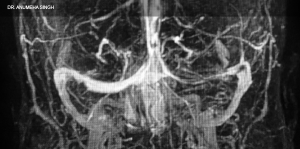

Dr. Anumeha Singh